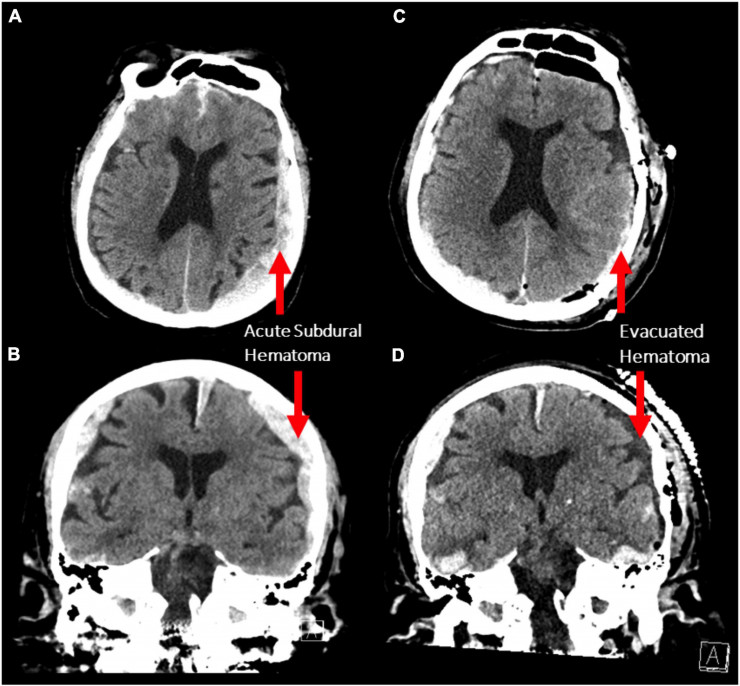

©Frontiers in Aging Neuroscience